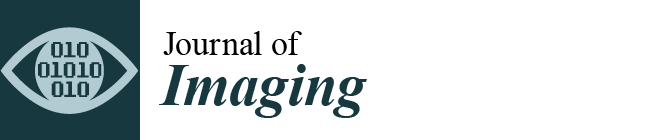

3.1. Inter-Observer and Intra-Observer Variability in μCT

3.1.1. Inter-Observer Variability

3.1.2. Intra-Observer Variability

4.1. Inter- and Intra-Observer Variability